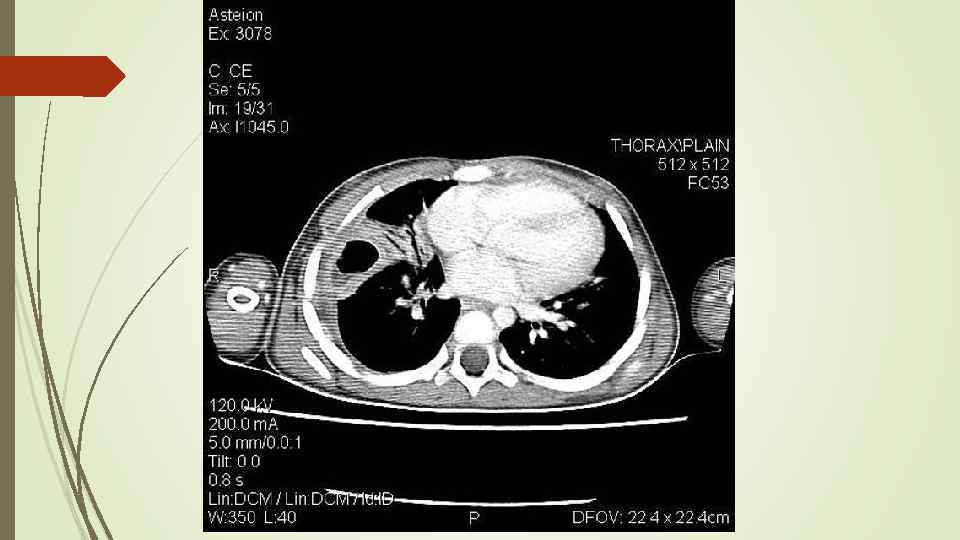

Плевральный выпот Скопление жидкости в плевральной полости (исключение гемоторакс, хилоторакс, пиоторакс) Транссудат Экссудат Плеврит

Плевральный выпот Скопление жидкости в плевральной полости (исключение гемоторакс, хилоторакс, пиоторакс) Транссудат Экссудат Плеврит